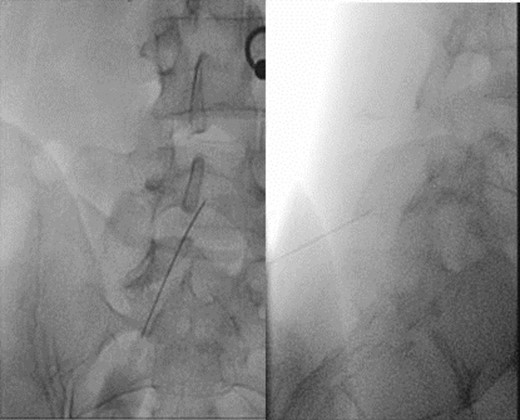

We then performed an infiltration with bupivacaine 0.5% above and below the S1 spinous process, at the level of pressure-evoked pain, with immediate improvement of painful hyperextension, and 8 hours of pain relief (Fig. 4).

Left: localization of pressure-induced pain. Middle and right: under fluoroscopic guidance, S1 perispinous infiltration.